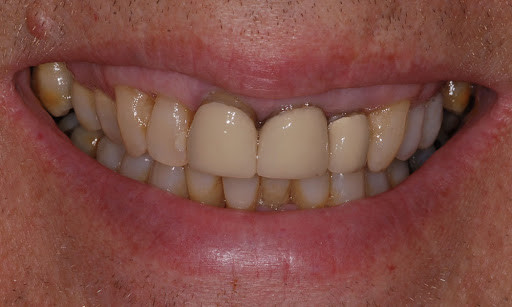

Identifying A Bruised Tooth

Most people don’t think of teeth when they think of bruises. Usually, it’s a black and blue knee versus a tooth. However, your teeth can become bruised, and it can be fairly painful. There are signs and symptoms you’ll need to be aware of, and you may need to visit the dentist depending on the severity. It may seem scary, but a bruised tooth is a common dental issue. And identifying a bruised tooth, is relatively straightforward.

CAUSES OF BRUISED TEETH

A bruised tooth is often caused by an injury to the tooth. Similar to a bruise on your skin, a bruised tooth is a reaction to excess pressure or force. While your tooth won’t turn black and blue like your skin, it can become discolored and turn a gray tint.

A bruised tooth is painful and may ache because the soft tissue and ligaments around your tooth essentially absorb the impact of the trauma or injury. Just like a bruise on your skin, the capillaries around the injured tooth burst. The capillaries then travel to the opening of the tip of the root, which gives the tooth a pinkish discoloration.

The pinkish discoloration may turn gray, which can be permanent. A gray tooth may mean that the pulp inside your tooth is impacted, resulting in a higher risk of infection or decay. This can result in the need for a root canal Brentwood. If your tooth does not turn from pink to gray, you may be in the clear. However, you should see the best dentist Brentwood has, as they will want to monitor your tooth and help you in identifying a bruised tooth.